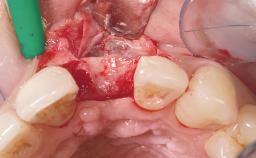

Late Flapless Placement of an Implant in a Maxillary Left Central Incisor Site

A 39-year-old male patient presented with a chief complaint of discomfort and gingival discoloration around his maxillary left central incisor. He was in good general health and was a non-smoker. His past dental history was significant because of the traumatic fracture of tooth 21 in a sporting accident at age 13. Initial dental treatment included endodontic therapy and a full-coverage restoration. The patient became symptomatic 5 years later, when structural failure of the tooth resulted in the dislodgment of the crown. Endodontic retreatment, apical surgery, and post-and-core restoration were performed.

Bone Augmentation Horizontal|Staged

Augmentation Materials Xenogenous|Membrane